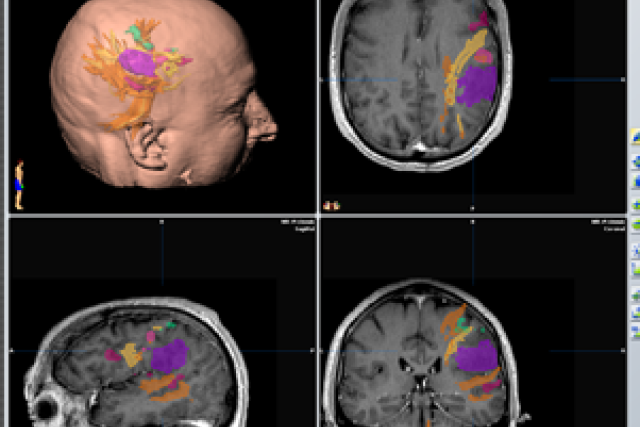

Functional MRI scanning fused to intra-operative neuro-navigation technology allows doctors to create a personalized virtual 3D model of a patient’s tumor (purple) relative to normal functional areas of the brain that control motor function (green) and language function (yellow/orange). This allows neurosurgeons to visualize the areas of the brain to avoid before going into surgery, so they can more safely take out tumors near areas that may previously have been considered inoperable. (Image courtesy of Dr. Linda Liau)

“Sometimes tumors are close to what we call the eloquent areas of the brain – the areas that control motor, sensory, or language functions,” she explained. “Often, neurosurgeons can’t take out tumors near these areas because they don’t know exactly where these areas are relative to the tumor.”

That’s where functional magnetic resonance imaging (fMRI), which allows brain mapping before surgery, comes in. “We’re one of the leading centers that does functional MRI scanning in conjunction with intra-operative brain mapping,” Dr. Liau said. “We’re able to use cutting-edge imaging technology and brain stimulation in real time to better inform our surgeries.”

In Widener’s case, the tumor was in the frontal and parietal lobes on the left side of his brain, in between his primary motor-sensory areas and encroaching upon language areas, which made the operation more difficult.

During a pre-surgery scan, Widener was asked to perform specific tasks that then caused the corresponding areas in his brain to light up on the brain scan. That helped pinpoint which areas to avoid during surgery.

Widener’s scan was then used to create a three-dimensional model of his brain. “It takes quite a bit of post-processing to really interpret those functional MRI scans to use them for surgical localization,” Dr. Liau said.

“It’s a very informative, interactive map – we’re able to map out not just the neurons, but also all of the fiber tracks connected to those neurons,” she said. Even so, she noted, “during surgery, we still have to stimulate the neurons in the brain to determine if they are working while we take out the tumor.”

That meant using functional mapping fused to intra-operative navigation during the surgery to precisely locate areas of the brain to stimulate and measure the response using electrodes. “For example, if I stimulate a specific area in the brain and that causes twitching in the face, arms, or legs on the opposite side, then I know that’s a primary motor area and to avoid it,” Dr. Liau said.